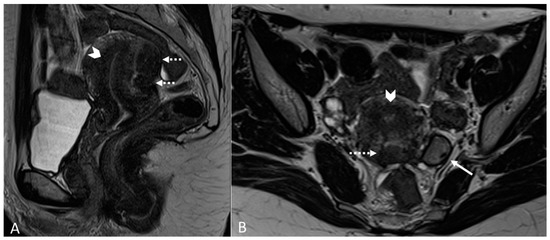

Generally, they appear hyperintense on fat-suppressed T1WI and T1WI (Figure 7 and Figure 8). The hyperintensity on fat-suppressed T1WI helps differentiate endometriomas from dermoid cyst and teratoma, which usually contain fat [51]. On T2WI, a variable signal can be obtained: a hypointense signal can affect variable portions of the cyst, sometimes also presenting a stratification, until a complete loss of the signal. This is called the shading sign and is correlated to the different state of hemoglobin degradation [52] (Figure 8). The T2 dark spot sign refers to hypointense spots in the wall of the cyst due to the presence of macrophages (Figure 9).

Figure 8.

Right tubo-ovarian endometriosis in a 25-year-old female patient with reported localized abdominal pain in the right iliac fossa, which increases intensity during the menstrual cycle. (A) Axial T2WI; (B) Axial fat-suppressed T1WI. Enlarged right adnexal cyst with incomplete septa denoting dilated tube (white arrows). The cystic content shows low signal intensity on T2WI and high signal intensity on fat-suppressed T1WI, consistent with hemorrhagic fluid.

Figure 9.

Diffuse internal and external adenomyosis in a 37-year-old female. (A) Sagittal T2WI; (B) Axial T2WI. Diffuse internal adenomyosis as demonstrated by diffuse hypertrophy of the JZ (white arrowhead in (A,B)), subserosal hypointense ill-defined mass in the posterior myometrium consistent with external adenomyosis (white dotted arrows in (A,B)), with associated deep endometriosis of posterior compartment. Left endometrioma with T2 dark spot sign (white arrow in (B)).